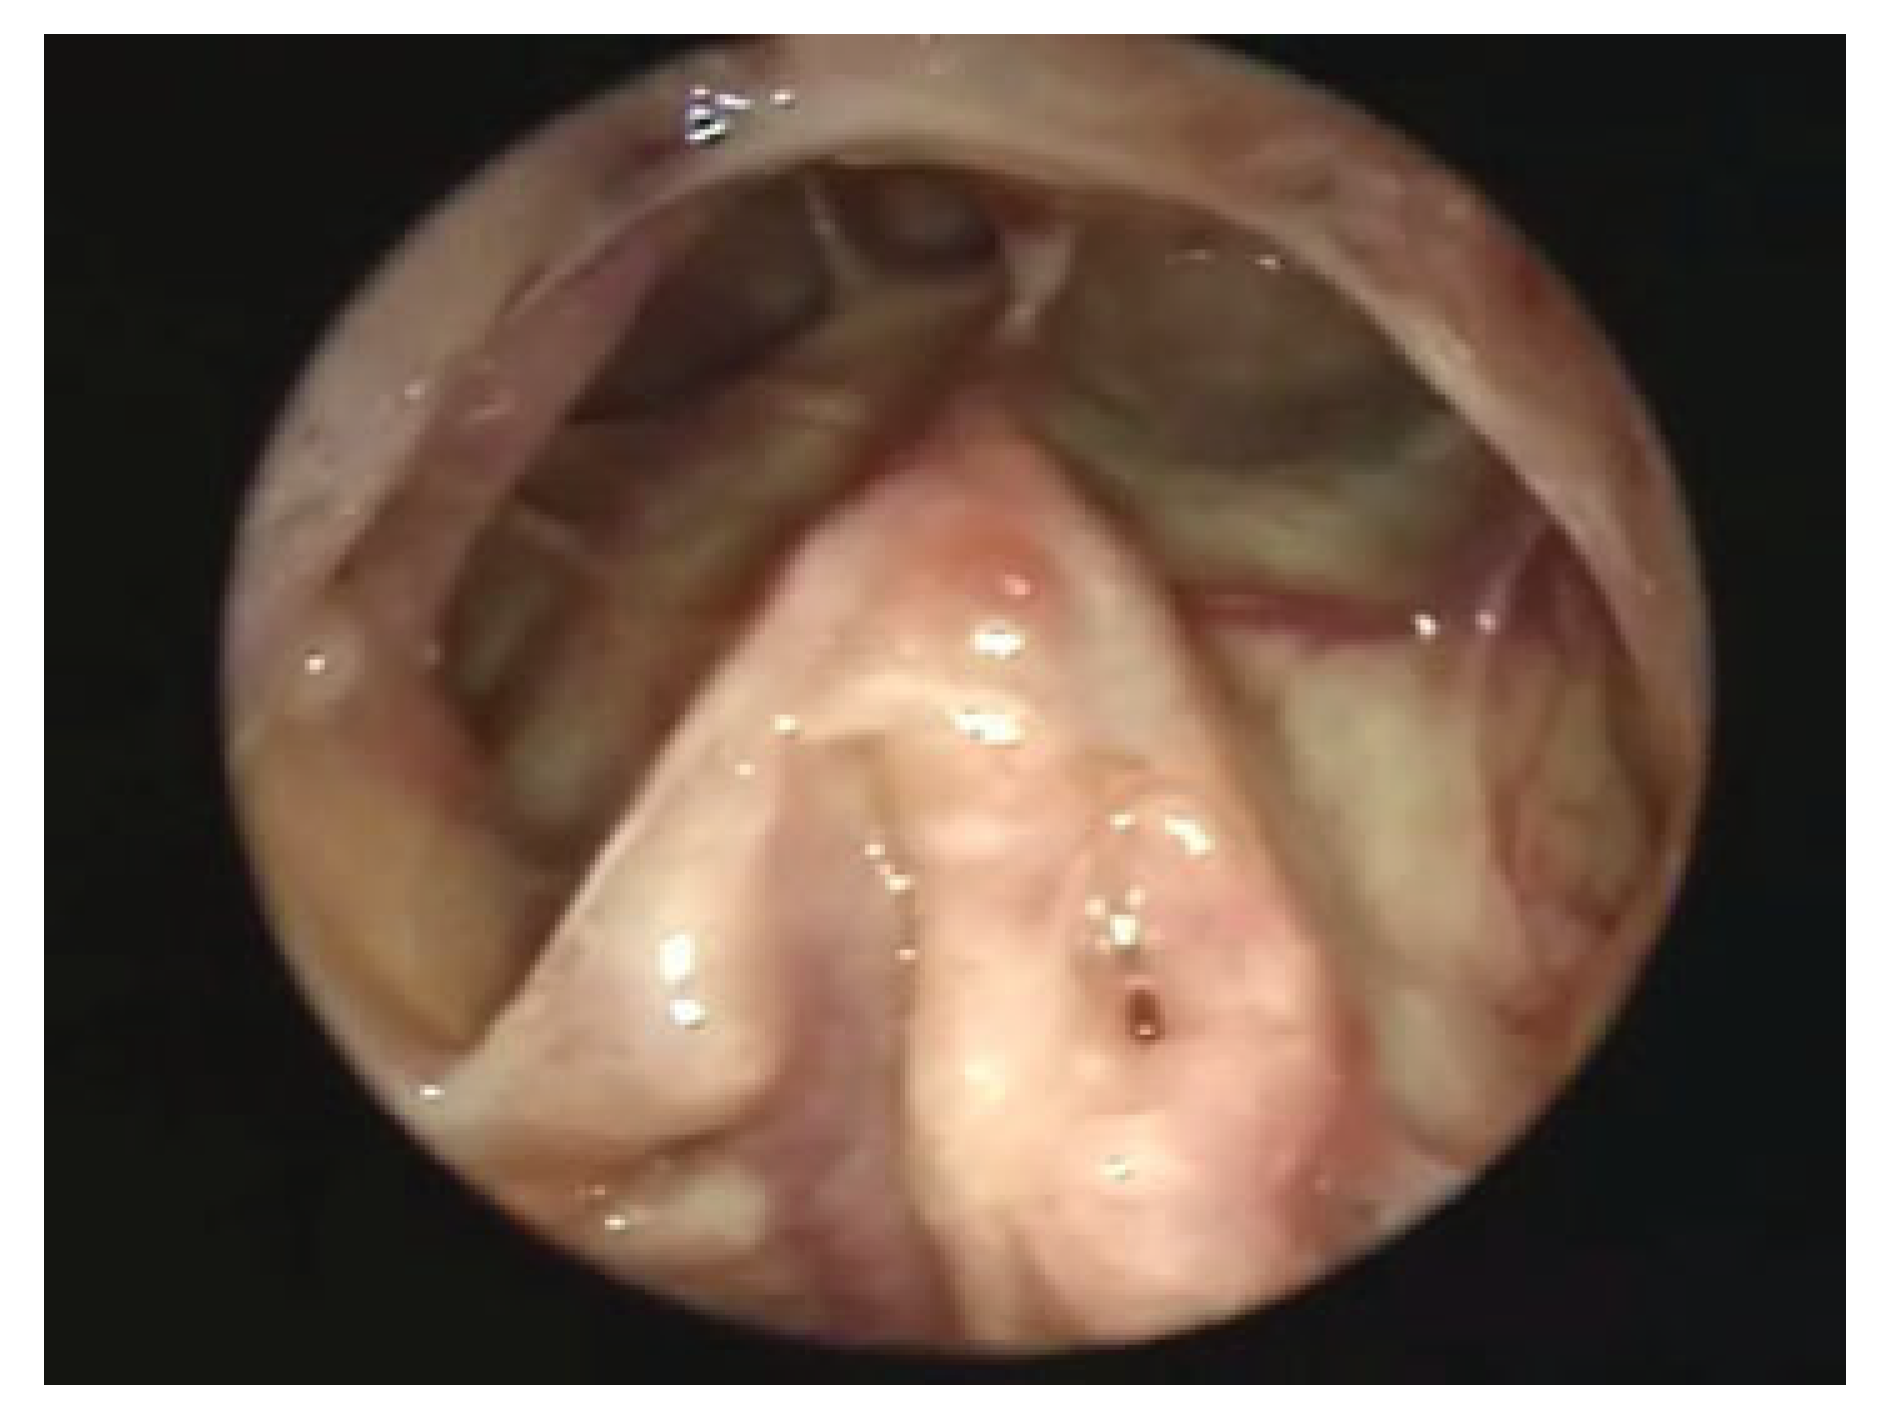

As noted above, there are two areas in which our radiologic assessments remain less than ideal. One is the evaluation of the frontal sinus outflow tract. The other is the posterior wall. The endoscope has proved helpful in both of these situations (Figure 2A–E). If there is a defect in the anterior wall inferiorly or of the supraorbital rim, a scope can be placed through a small incision (trephination approach) and the outflow tract can be visualized using angled lenses. If the bone is intact, a small medial incision below the brow will provide access to the medial inferior bone. A small trephination of the sinus can be accomplished with a burr, and a scope can then be placed into the sinus. Similarly, using the same trephination approach, a scope can be used to assess the posterior wall [14]. In the authors’ experience, on more than one occasion, brain has been encountered in the sinus, herniating through a nondisplaced fracture. When used in this manner in the acute trauma setting, trephination combined with endoscopic visualization can alter the treatment of frontal sinus injuries.

Figure 2.

Trephination approach for endoscopic assessment of the posterior wall. (A) Incision. (B) Exposure of fracture. (C) Exposure of sinus. (D) Exposure of posterior wall of frontal sinus. (E) Repair.